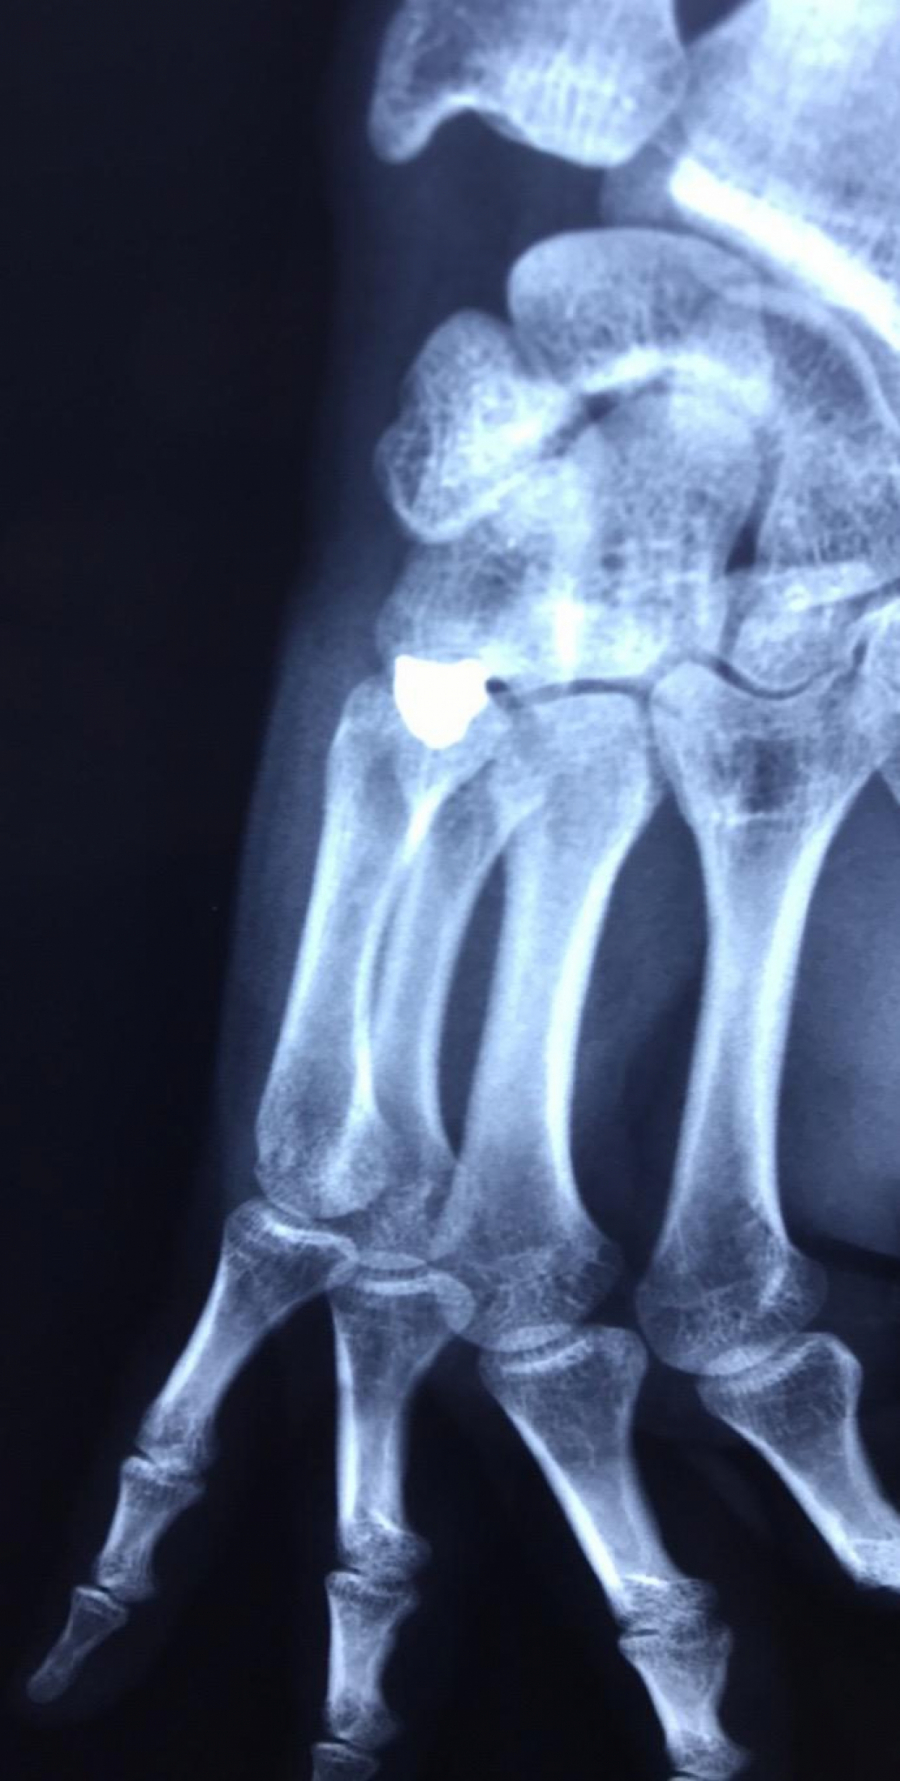

OBJAVLJEN RENDGENSKI SNIMAK Ovo je metak koji je izvađen iz šake srpskog mladića (FOTO)

U KBC Gračanica Miloš S. (21) izvađen metak koji je bio u šaci.

Ovde možete pogledati i rendgenske sinimke šake ranjenog mladića.